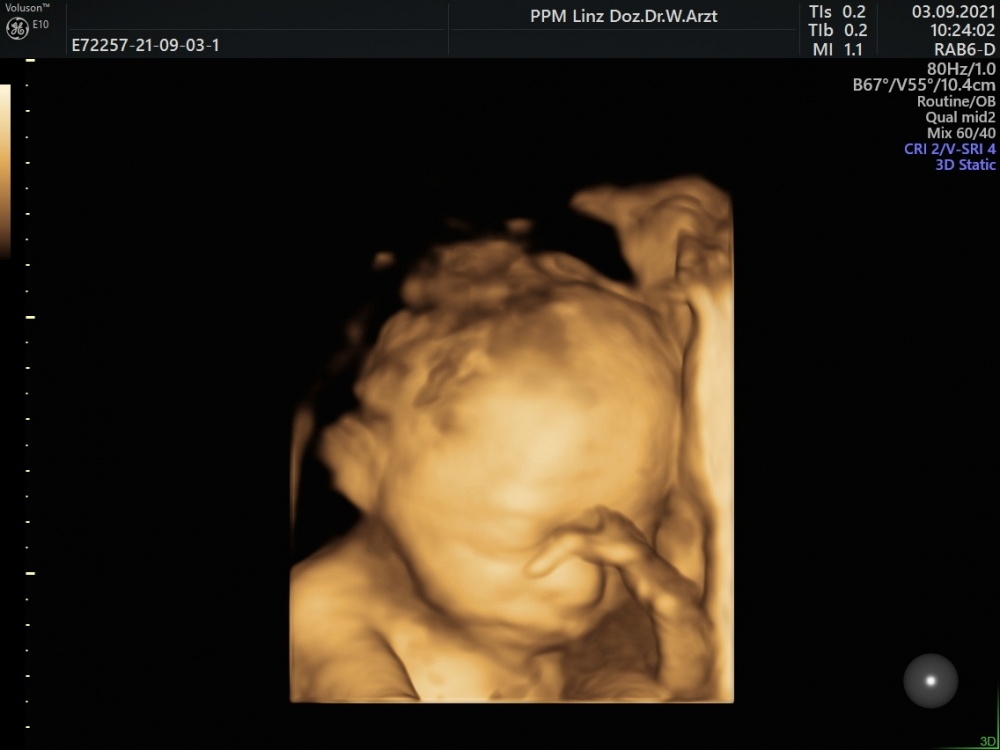

Mein Termin beim Organscreening war super, die Ärztin hat sich wieder viel Zeit genommen. Sie hat 2 Mal mit kurzer Unterbrechung dazwischen geschallt und auch vaginal geschaut damit sie alle Daten aufnehmen konnte.

Es ist alles absolut unauffällig und entspricht der Norm. Bin wirklich wieder sehr erleichtert.

Anbei noch ein Bild. 22+4

m59o25t7elzd.jpg

@Jigsawdani soooo ein liebes Bild und toll dass alles in Ordnung ist!

Danke an alle 🥰 ich schau mir die 3d Bilder die ganze Zeit an, hab schon oft gehört dass man da wirklich gut erkennen kann wie das Baby dann aussehen wird. Ich finde es sieht jetzt schon aus wie mein Freund wenn er schläft 😂

@elara Tolle Fotos habt ihr bekommen, das 3D schaut schon echt cool aus 😍😍